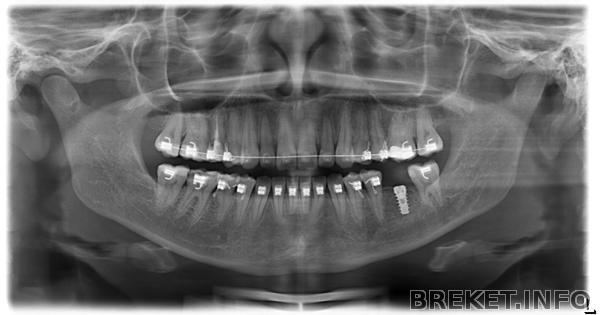

Урррраааа! Хотела поделиться со всеми своей радостной новостью Сегодня на приеме у орта узнала, что мне будут снимать брекеты через месяц, максимум два! Весь день успокоиться не могу, смотрю клипы, вижу красивые улыбки и воображаю, как после снятия буду делать реставрацию, отбеливание и т.д.

Пока что брекеты ношу 1 год и 3 месяца. Думала, буду носить намного дольше. Уже не терпится сделать фотки "После"